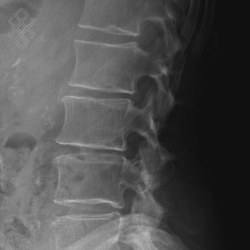

Radiographie du Rachis lombaire

La durée de l'examen est d'environ 5 minutes. Un ou plusieurs clichés radiographiques seront effectués. Le manipulateur vous positionnera en fonction de l'incidence radiologique à réaliser. Sauf indication contraire, il sera important de ne pas bouger durant la prise de clichés.